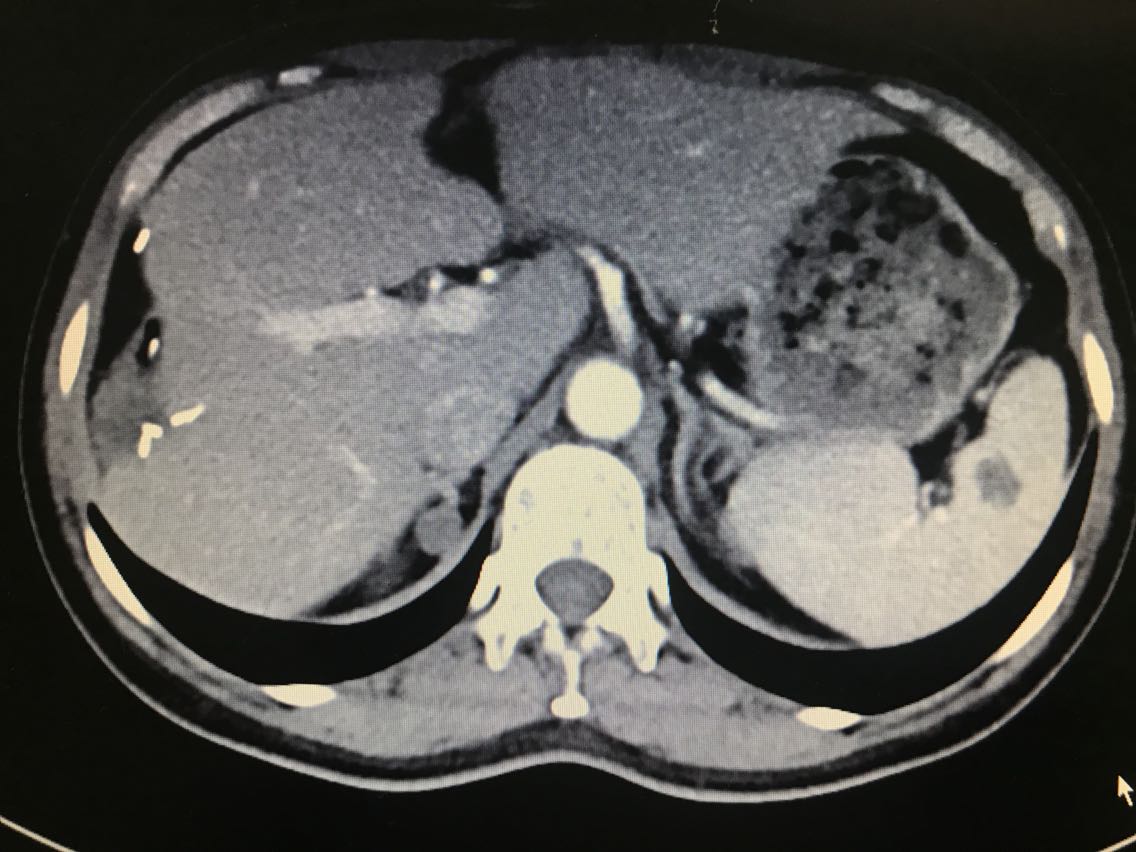

查体无特殊。 辅助检查: 全腹CT:右侧肾上腺占位。

诊断:1.原发性醛固酮增多症(右侧优势侧)2.右侧肾上腺结节 治疗:腹腔镜右肾上腺肿瘤切除术 术中见:右侧肾上腺肿物与肾周紧密粘连,金黄色,约1.0*1.8*1.0cm大小。剖视肿瘤为鱼肉状实性肿物。